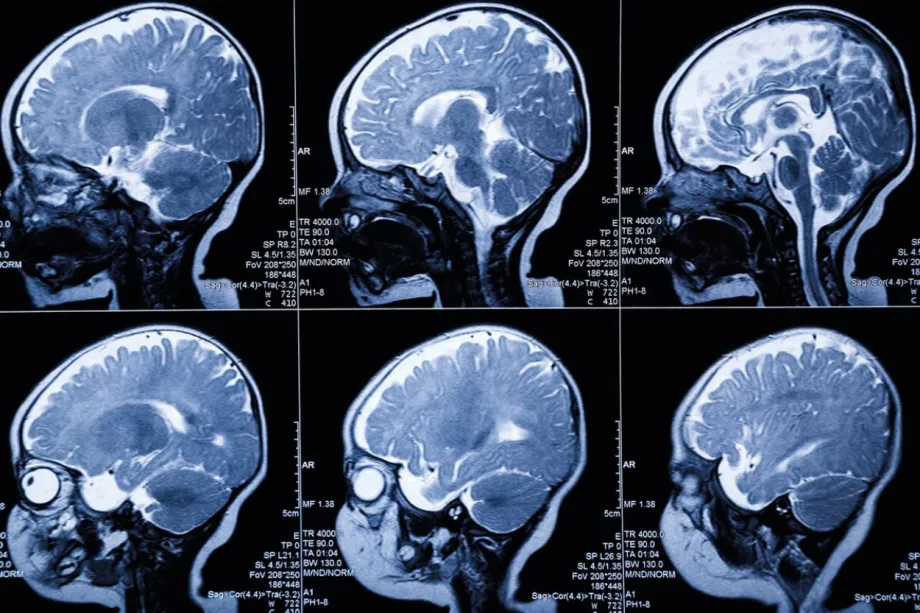

He said: “When a child first becomes poorly with a brain tumour, they have a brain scan, usually MRI.  The MRI scans are looked at by highly trained doctors (radiologists) who interpret the images to make a diagnosis of tumour type, but it can often be difficult to make an exact diagnosis due to overlaps in the scan appearances between different types of tumours.”

He said: “Our approach has been to use a technique called ‘radiomics’, which is a computational image analysis technique that allows us to detect features in the scan images that are not visible to the naked eye.  These ‘hidden’ features can then be assessed using artificial intelligence approaches that allow improvements in diagnostic accuracy.”

MRI scan images of a child's brain.

His team has developed a computer programme trained on MRI scans and patient data. Even with a small dataset, it has already shown it can tell apart the two main types of ependymoma (PFA and PFB), and even distinguish between two subtypes of PFA (PFA1 and PFA2). This is important because researchers think that these tumour subtypes could have different responses to treatment.